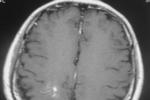

1.腦血管造影:病灶隻在靜脈期顯影,可見數條擴張的髓靜脈扇形匯集成一條擴張的中央靜脈幹,從中央靜脈幹再向淺靜脈系統,深靜脈系統或硬膜竇引流,無異常動靜脈短路征象,動脈期和腦血流循環時間正常.2.CT掃描:平掃多正常,在增強掃描上可見腦實質內一條粗線般的增強影流向皮質和腦深部,其周圍無水腫和團塊占位,有時也可表現為圓點狀病灶,這種粗線狀或圓點狀影是中央靜脈幹的影像.3.MRI掃描:其表現與CT所見相似,在T1加權像上病灶為低信號,在T2加權像上多為高信號,少數為低信號,註射對比劑後病灶呈現典型的放射樣星形或蜘蛛樣.